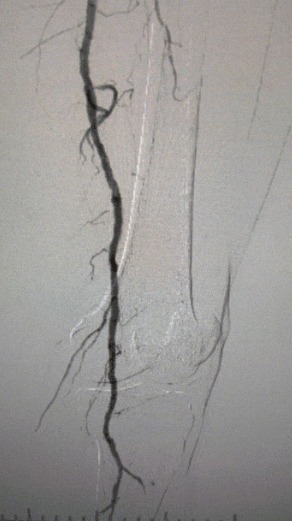

· Körperliche Untersuchung: Schwache Femur impulse; fehlende Popliteal-und Dorsalis-Pedis-Impulse; Geschwür am linken ersten Zeh; Nekrose am rechten ersten und zweiten Zehen

· Präoperative Bildgebung: Schwere, diffuse verkalkte Stenose in bilateralen Arterien der unteren Extremitäten

Angesichts des komplexen Gefäß zustands haben wir das ThorCrack Periphere IVL-Ballon dilatation katheters ystem ausgewählt. Aufgrund der begrenzten Toleranz des Patienten wurden inszenierte intervention elle Eingriffe an beiden unteren Gliedmaßen durchgeführt.

Chirurgisches Ergebnis